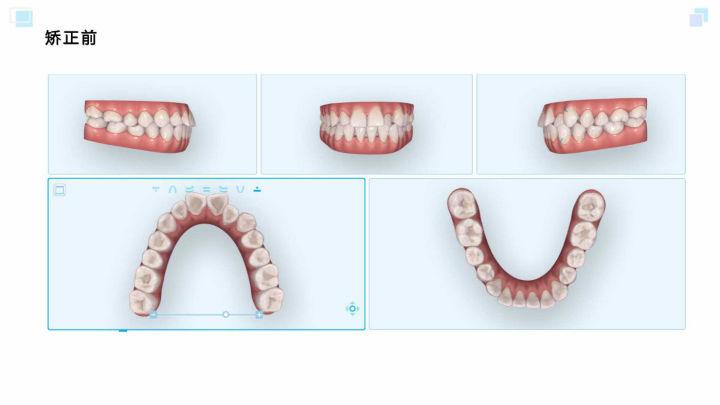

正畸前口内照

iTero口扫照